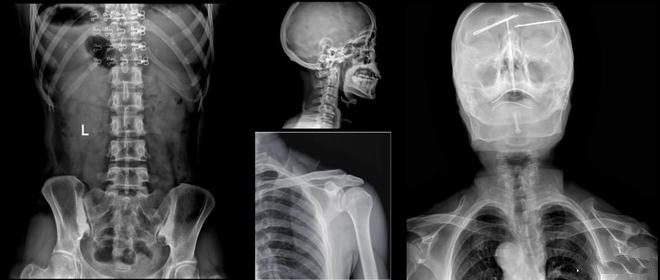

美诺瓦Staray双立柱智能DR采用自研核心数字医学影像链技术,成像速度快,放射技师即刻在屏幕上观察到高清图像,病灶一览无余,辅助医生进行更加精准的诊断,AEC自动曝光控制,让拍摄剂量控制更加轻松,省时省力。